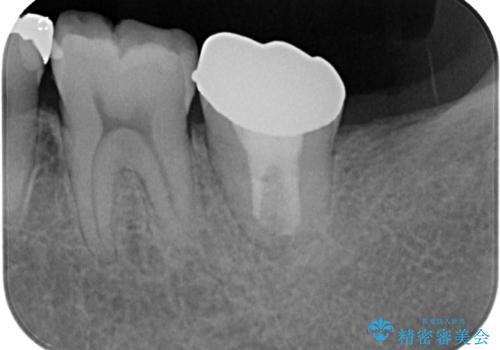

上顎の歯をアンカースクリューを用いた部分矯正により位置を修正し、根管治療後にPGAクラウンにて補綴治療を行うこととしました。

歯列が整ったことで咬み合わせが非常に安定しました。